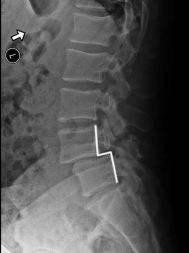

When we look at the spine from the side, we can imagine a scotty dog. It is outlined above. The pars fracture is seen as a collar around the dog's neck. Instability and movement can cause the neck to widen. We will see this below in an X-ray example.

X-RAY SHOWING A PARS FRACTURE DEFECT